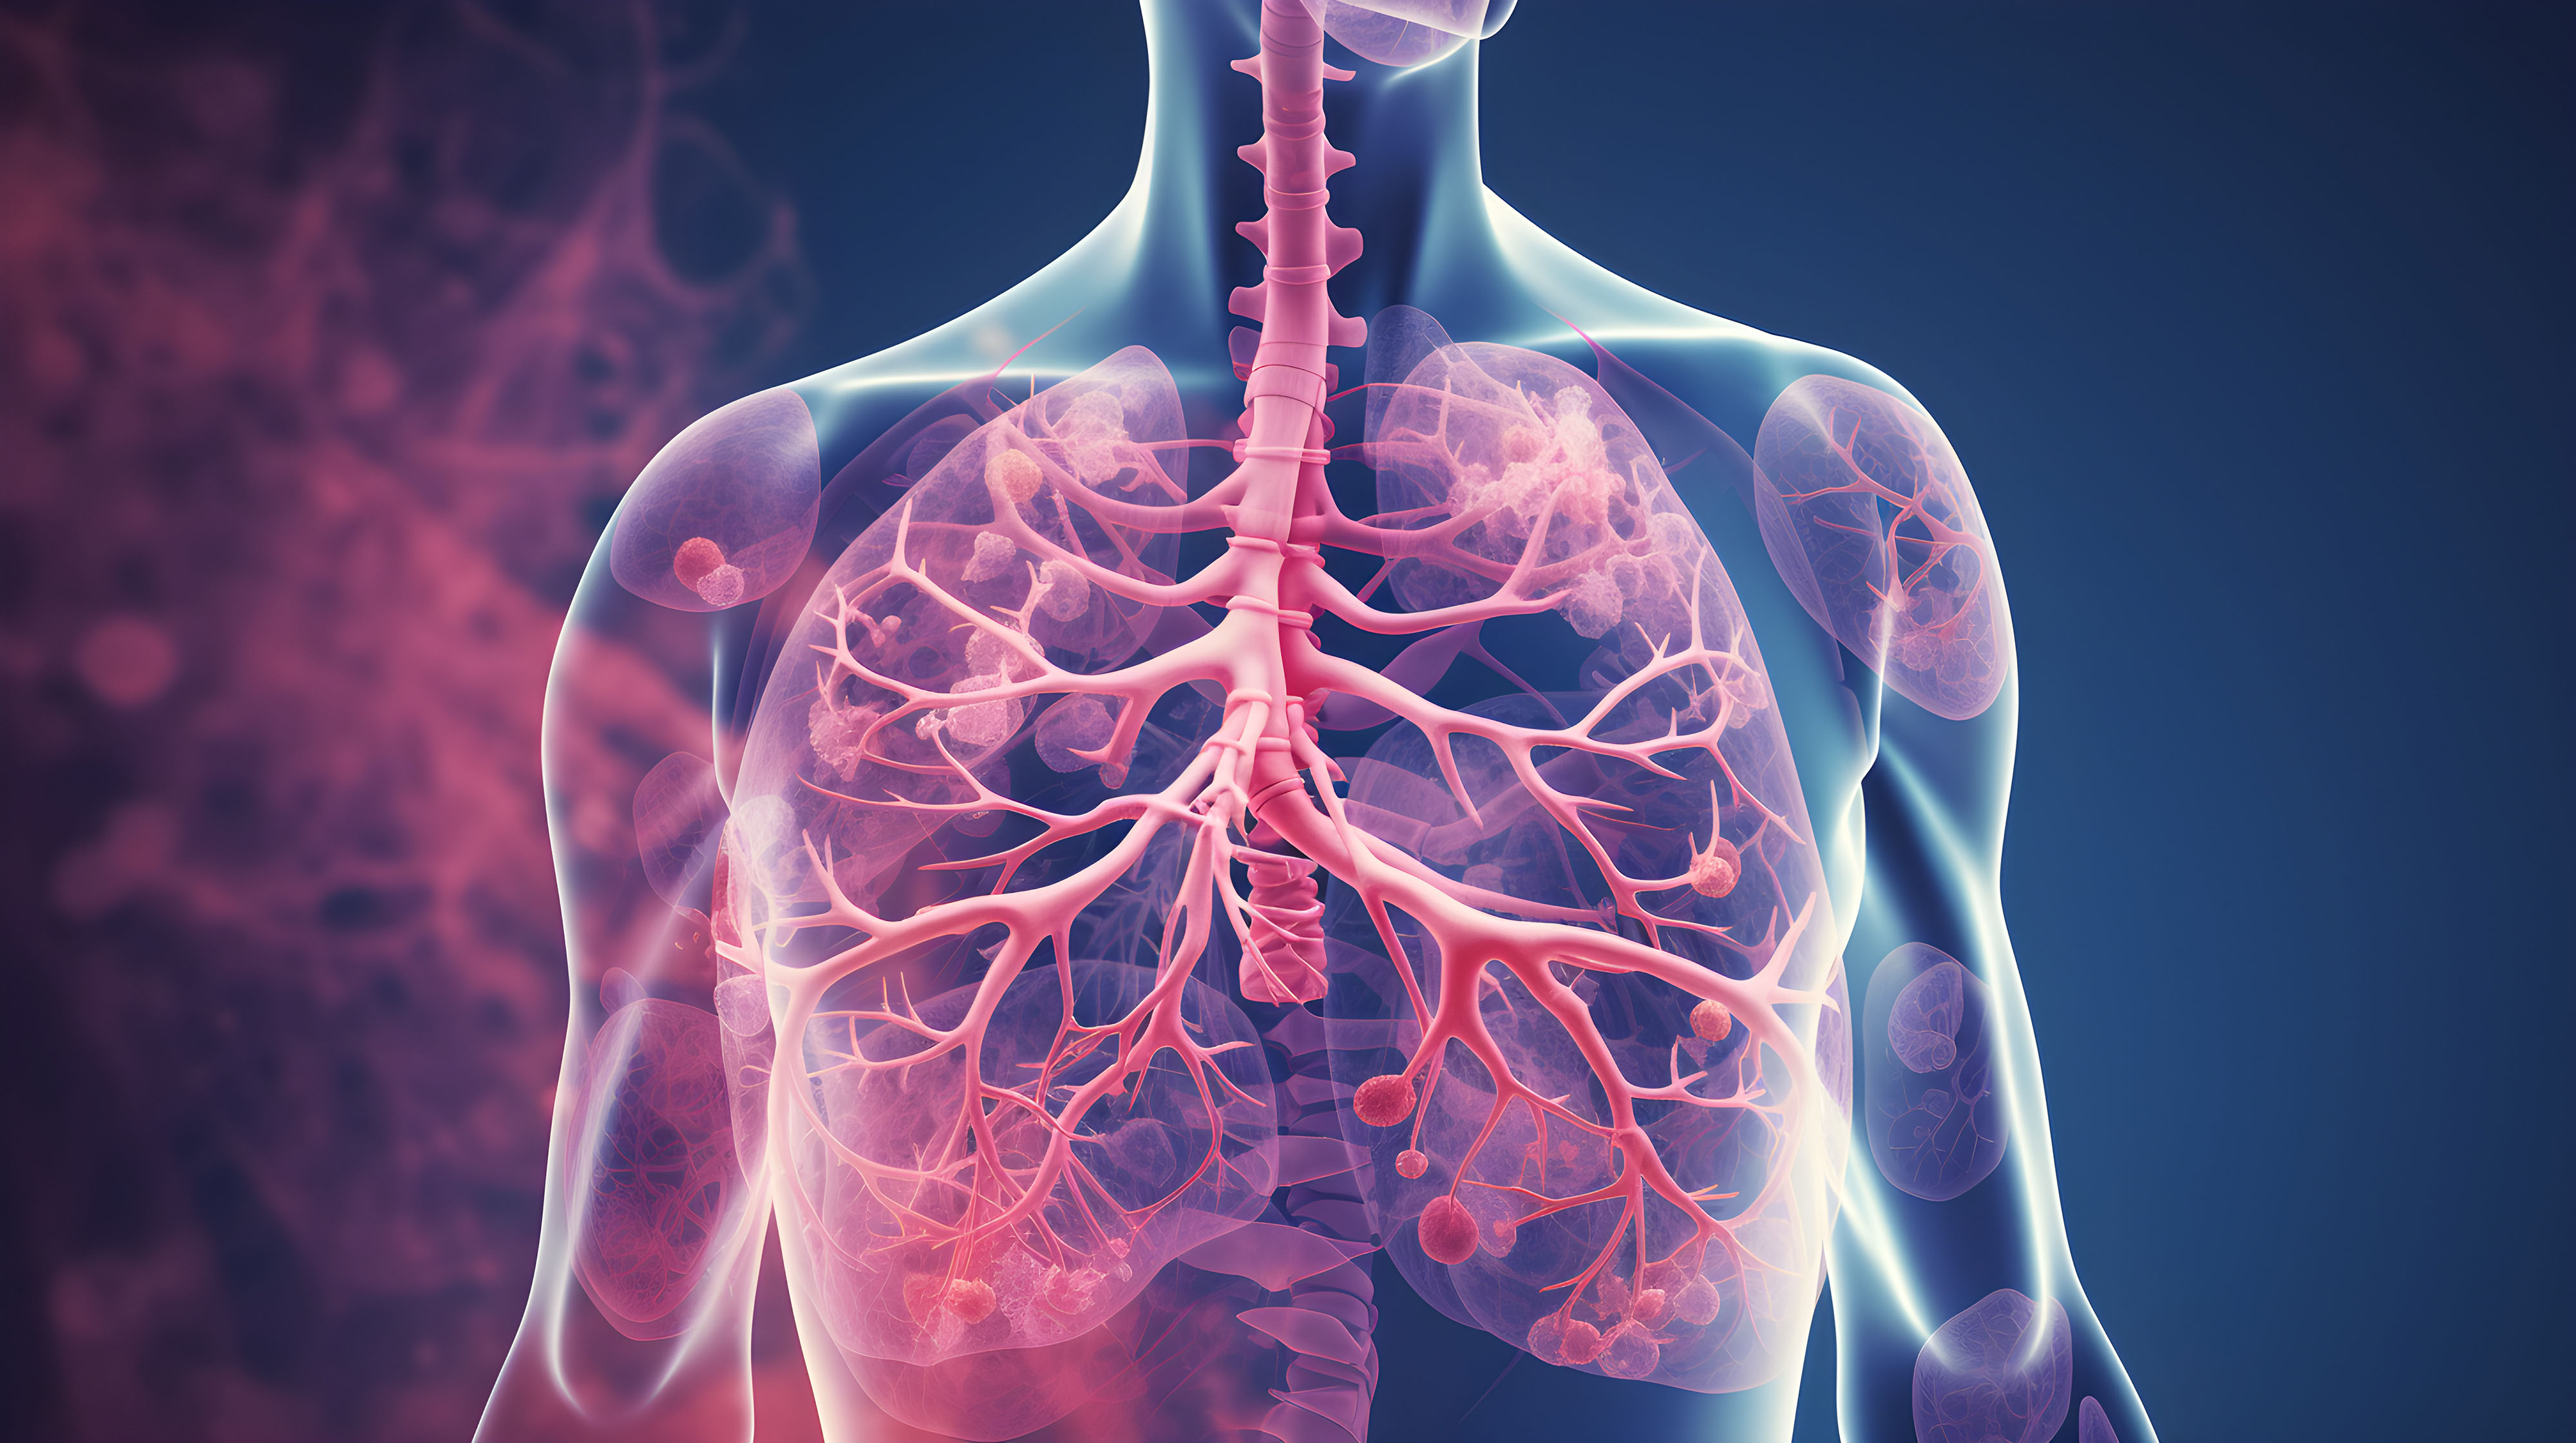

From Embolus to V/Q Mismatch

When a clot lodges in the pulmonary arteries, it instantly cuts off blood flow to regions of lung that remain well-ventilated. Air still enters the alveoli, but oxygen molecules have no red blood cells waiting at the capillaries. This creates dead space ventilation—ventilation without perfusion.

Early gas exchange changes:

The patient’s PaO₂ begins to fall because less blood is participating in oxygen uptake. Meanwhile, PaCO₂ may look deceptively normal, because the patient compensates with tachypnea and high minute ventilation.

EtCO₂ clue:

Because exhaled CO₂ reflects perfused alveoli, and many alveoli are no longer perfused, EtCO₂ drops disproportionately compared to PaCO₂. The widened PaCO₂–EtCO₂ gap is a red flag for dead space [5,6].

Pulmonary Vascular Resistance (PVR) and RV Afterload

The clot doesn’t just steal oxygen exchange; it also spikes resistance in the pulmonary circuit. The right ventricle (RV) is built for low-pressure pumping into a compliant pulmonary bed. It can handle gradual increases (like in chronic lung disease), but it is not designed to face a sudden wall of resistance.

RV dilation:

Acute obstruction increases PVR → RV cavity dilates to maintain stroke volume.

Septal shift:

As RV pressure rises, the interventricular septum bows into the LV cavity, impairing LV filling. Stroke volume falls, and systemic blood pressure drops [7].